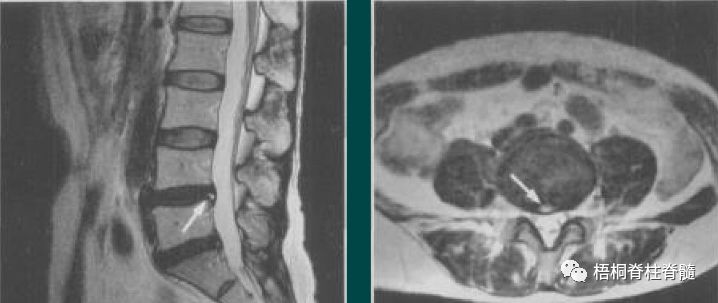

盘源性腰痛:有长期久坐或腰部受累史,腰痛没有固定痛点,弯腰恐惧,甚至有些患者出现腹股沟区的疼痛。CT上可见“真空征”,MRI常表现为“HIZ区”,矢状面T2加权像上纤维环后方见信号增高区域,它与髓核的影像分离且信号高于髓核。